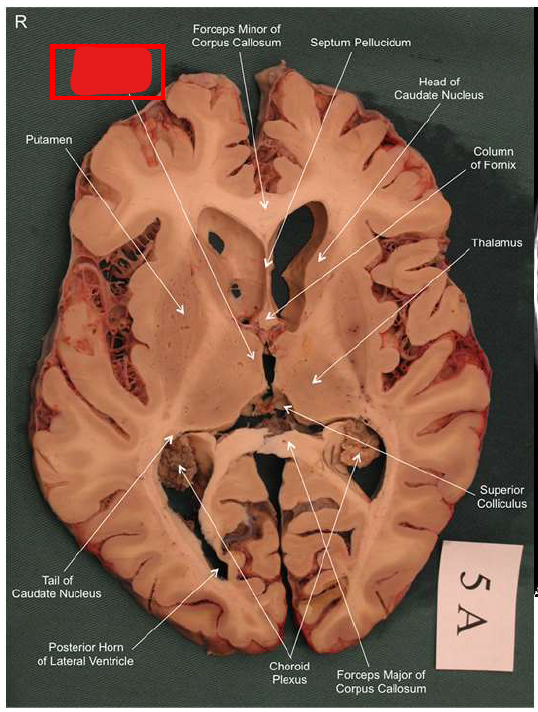

What is the fornix of the hippocampus?

Hippocampus output pathway (C-shaped)

Connects hippocampus to hypothalamus/mamillary bodies

Carries information to and from hippocampus

Important for memory consolidation and retrieval

How does the hippocampus form memories?

Association areas activate the hippocampus, which reverberates in the Papez circuit until information is stored permanently

Hippocampus → fornix → mamillary bodies → anterior thalamic nucleus → cingulate cortex → hypothalamus